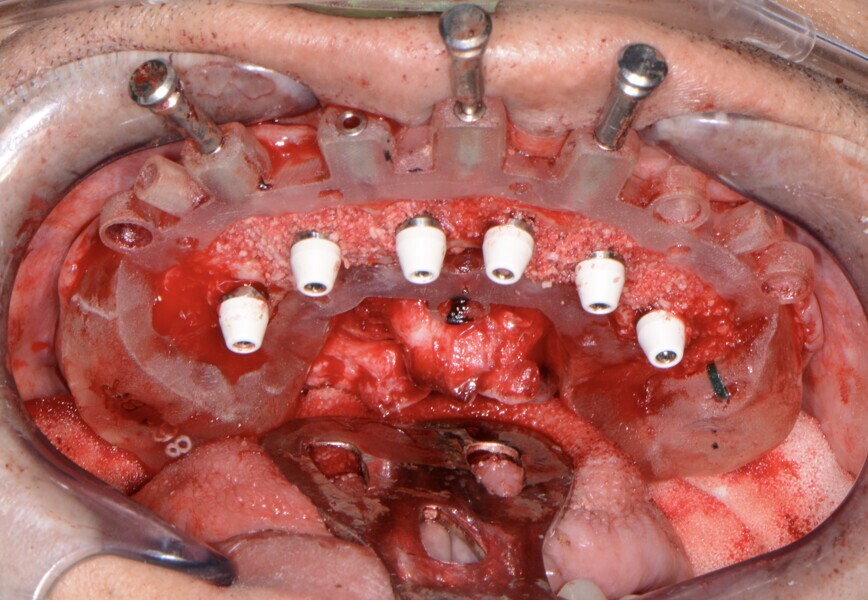

Fig. 13: Implants with corresponding multi-unit abutments.

Fig. 18: Implants with corresponding multi-unit abutments.